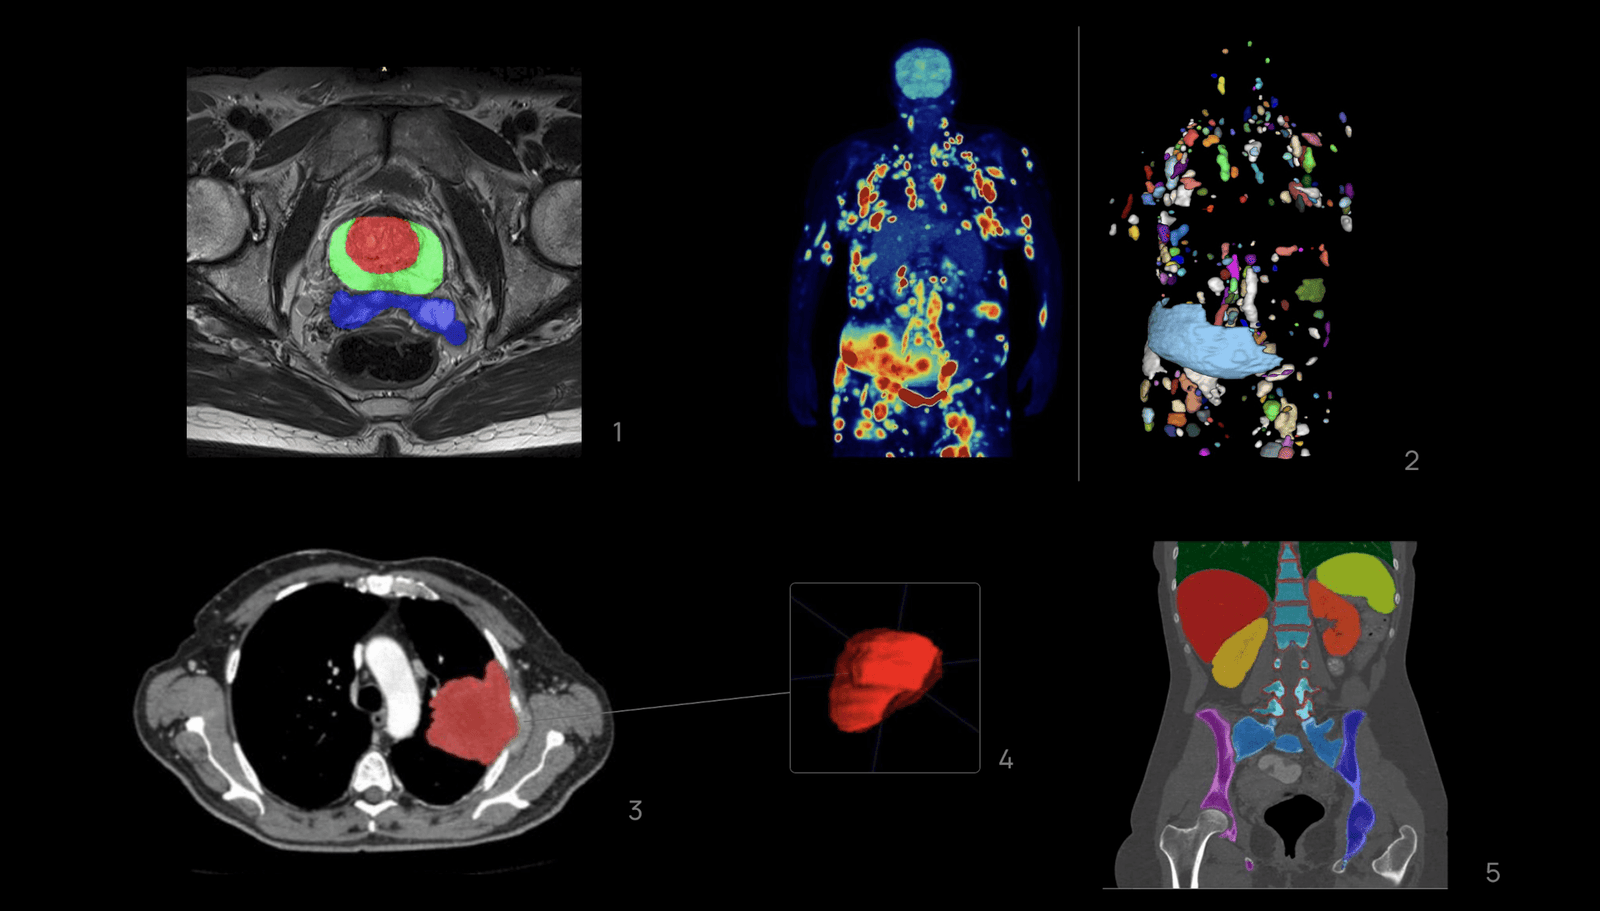

The medical AI segmentation process involves precisely identifying and delineating a region of interest (ROI) within an image. In medical image segmentation AI, these ROIs may include lesions, organs, healthy tissues, or structures, delineated in one or multiple imaging modalities, such Magnetic Resonance Imaging (MRI), Computerized Tomography (CT) or Positron Emission Tomography (PET), among others.

For this reason, a standardized segmentation process is systematically implemented in every study we manage at our company, leading to the definition of reproducible and standard protocols refined to each specific use case. Not only the segmentation of a lesion is important, but also its surrounding organs and tissues. For instance, in AI-driven solutions for overall survival (OS) prediction in lung cancer, not only is the lesion ROI considered, but also nearby structures such as lungs, heart, bone/calcium, liver, metastasis, among others.

1-Segmentation of the central zone, peripheral zone of the prostate and seminal vesicles on Axial T2-wheited magnetic resonance imaging.

2-Whole body 18-FDG PET/TC imaging exam of a patient with DLBCL in the coronal plane(left) and segmentation mask where every lesion is a unique label (right).

3, 4-Segmentation of the left lung tumor mass on axial Computerized Tomography slices with 3D reconstruction.

5-Segmentation of various anatomical structures in a coronal plane on a Computerized Tomography study.